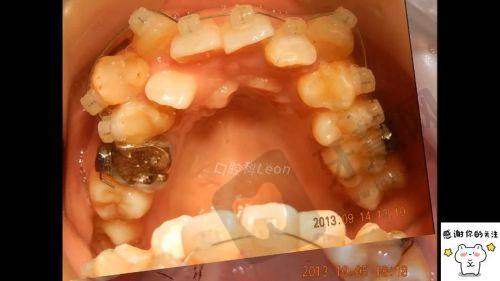

正畸方式选择:该方案提供多种正畸方式。金属托槽矫正价格在 8700 - 15000 元起,是传统且经济的方式,适用于多数牙列不齐病例,通过金属托槽和弓丝配合调整牙齿位置;陶瓷托槽矫正费用约为 12600 - 20000 元起,美观性优于金属托槽,适合对美观有要求的患者;隐形矫正价格区间在 25000 - 40000 元起,采用数字化定制矫治器,几乎隐形、佩戴舒适,患者可自行摘戴,不影响日常生活和饮食;舌侧矫正价格在 43000 - 80000 元起,将矫治器安装在牙齿内侧,完全隐形,但对医生技术要求高。

长春现代口腔快速正畸方案 29200 元起顾客实例

小李是年轻上班族,牙齿牙列不齐影响自信心,选择长春现代口腔快速正畸方案 29200 元起,医生为其制定陶瓷托槽矫正方案,正畸过程中定期检查和调整,小李严格按要求佩戴牙套和注意口腔卫生,牙齿逐渐变整齐,面部美观度提升,他对治疗成效满意,觉得价格划算。小张是学生,牙齿地包天,接受该方案治疗,医生采用金属托槽矫正方式,经过两年多矫正,地包天问题明显改善,咬合功能修复正常,他表示医生和护士特别关心他,感受到专精和温暖。这些实例表明该方案能有效解决牙齿畸形问题,在价格、成效和服务等方面获顾客认可。